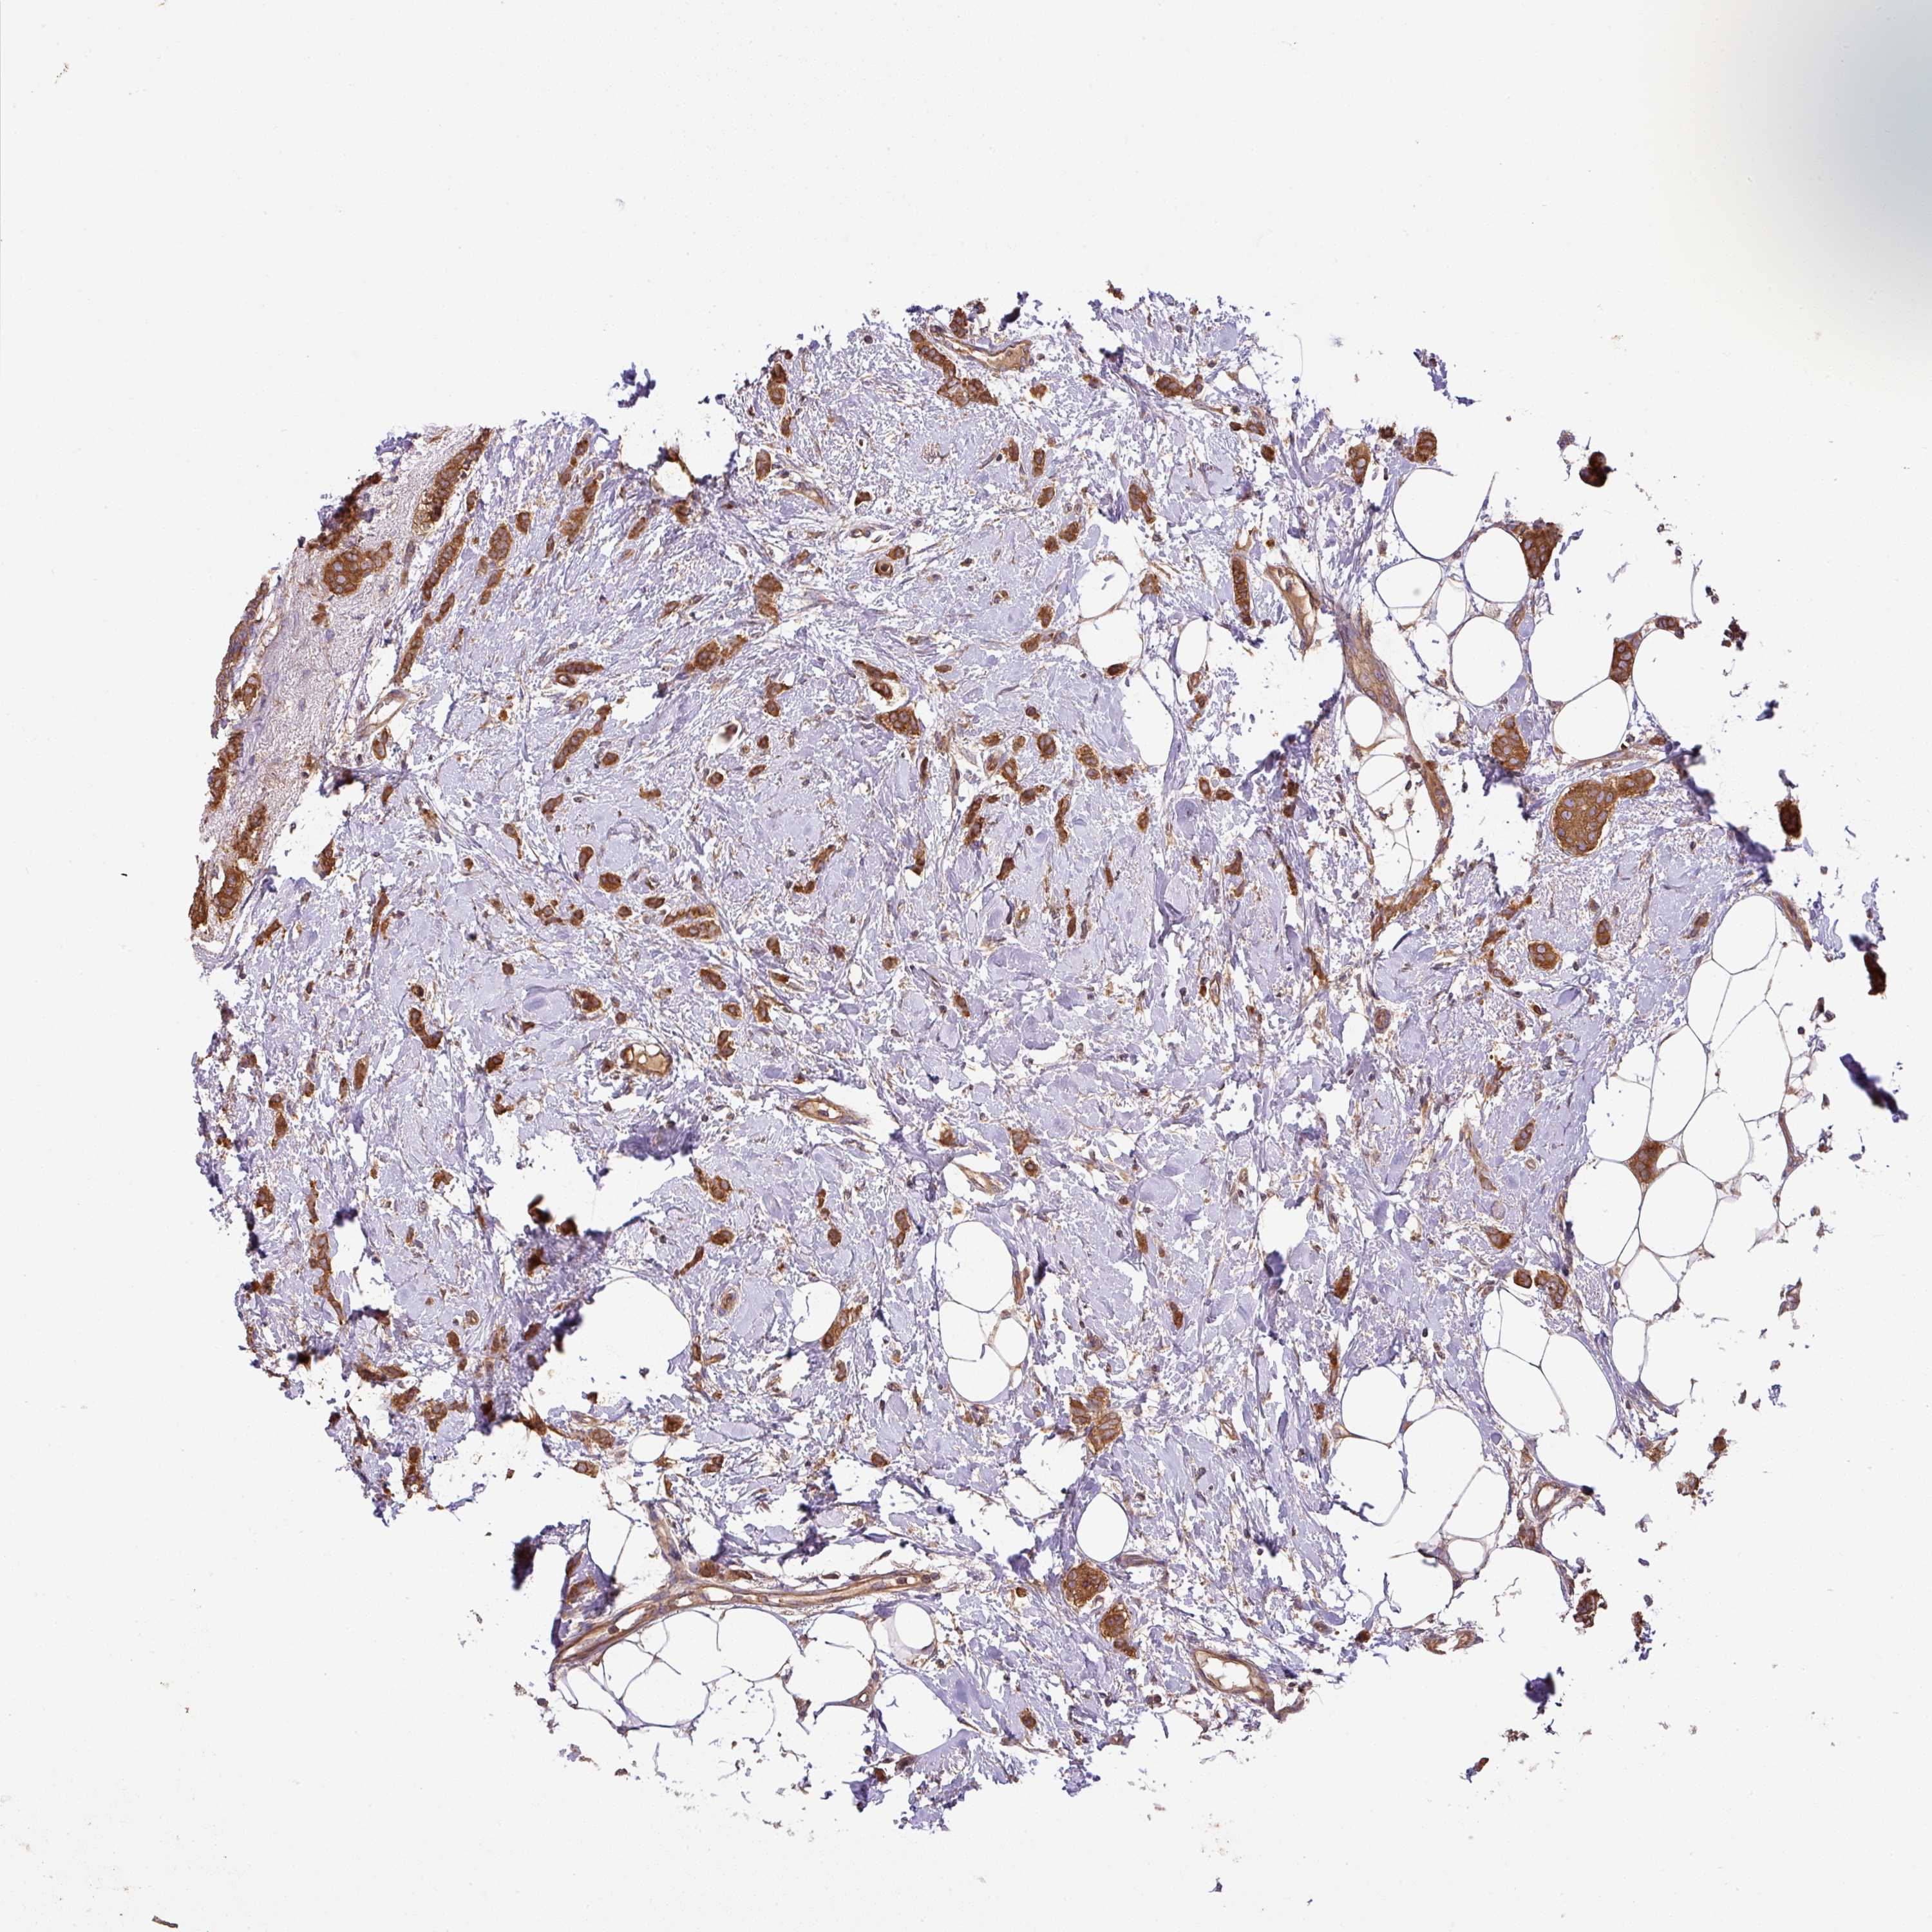

CANCER BREAST CANCER Show tissue menu

BRCA TCGA BRCA VALIDATION PROTEIN EXPRESSION